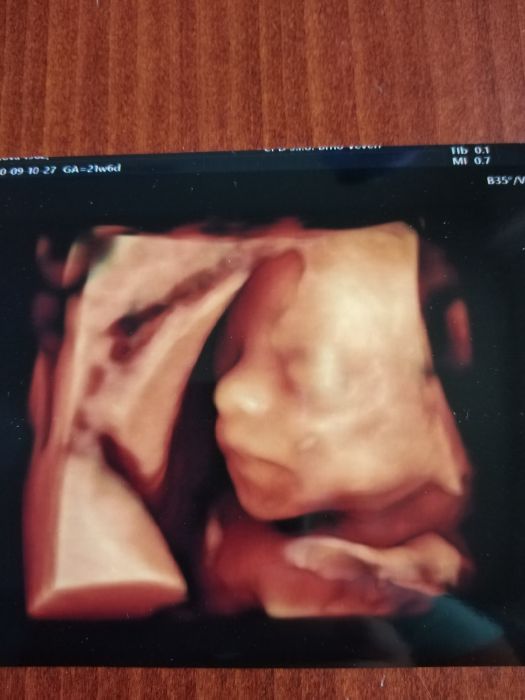

Ahoj holky, včera jsem byla na screeningu. Mimčo je zdravé a větší. Však má taky být po kom, jak poznamenal dr. Nicméně mi řekl, že nemám šanci na přirozený porod, což mě teda docela rozhodlo. Sice jsem po cs, ale tajně jsem doufala, že by to mohlo vyjít. Mám prý hrozně tenkou dělohu v dolním segmentu a hrozí mi ruptura dělohy.

Teď se musím prý hlídat. Nevím, co to znamená a co mě čeká... Dle fotky mimčo vypadá jako 100% kopie dcery

Dasho, děkuji za fotku te zavinovačky. Ty ještě nevíš pohlaví toho miminka? Vypadá kouzelně.